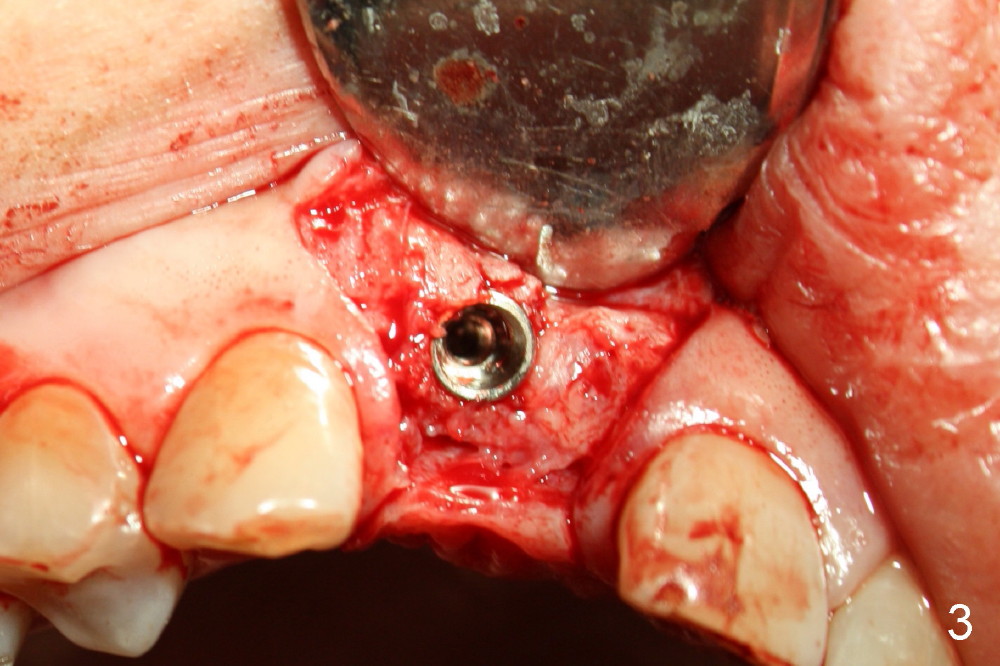

To increase buccal soft tissue bulk, the transverse incision is made lingual to the original socket (Fig.2 *). When the flaps are raised, the alveolar ridge appears to be deviated buccally; the implant (3.8x14 mm, insertion torque ~ 35 Ncm) also looks to be tilted too buccally even though it is placed in the middle of the ridge (Fig.3). An angled abutment (3.9 mm, 25º, 2 mm cuff, Torx A) has been adjusted buccally (Fig.4). The immediate provisional looks long (Fig.5). When the buccal flap is modified (Fig.5 insert) and sutured (Fig.6), the provisional looks to be tilted buccally. A custom Zirconium abutment should be used later on. All of these difficulties are due to delayed implantation with bone atrophy and are avoidable using immediate implant technique. Or check occlusion at the initial stage of osteotomy.